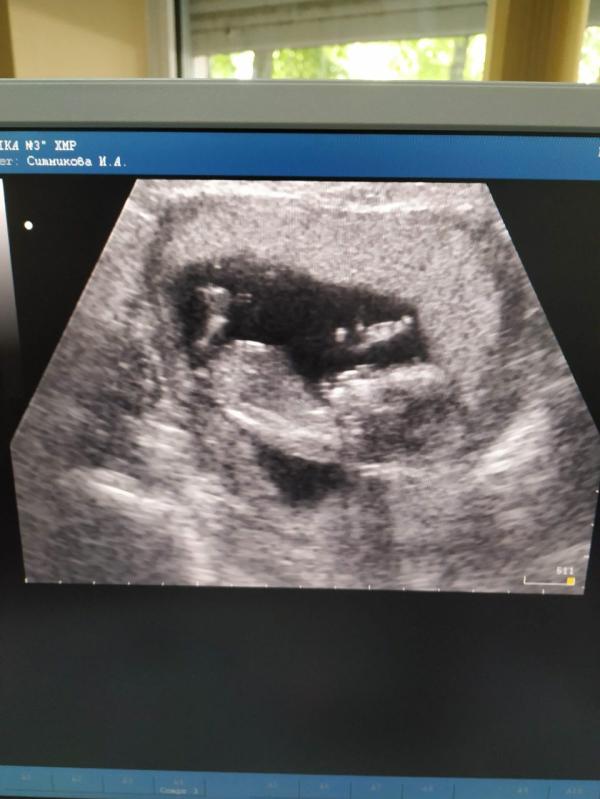

🎈 Беременность по счёту - 1

🔢 Роды по счёту - 1

📝Срок на момент родов - 40 недель 2 дня

👇Предлежание - головное

➰ Обвитие - нет